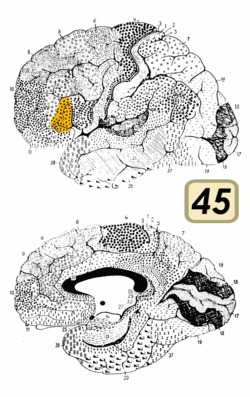

Brodmann area 45.png

Brodmann area 45 (BA45), is part of the frontal cortex in the human brain. It is situated on the lateral surface, inferior to BA9 and adjacent to BA46.

This area in humans occupies the triangular part of inferior frontal gyrus (H) and, surrounding the anterior horizontal limb of the lateral sulcus (H), a portion of the orbital part of the inferior frontal gyrus (H). Bounded caudally by the anterior ascending limb of the lateral sulcus (H), it borders on the insula in the depth of the lateral sulcus.

In terms of cytoarchitecture, it is bounded caudally by the opercular part of inferior frontal gyrus (Brodmann area 44 (BA44)), rostrodorsally by the middle frontal area 46 (BA46), and ventrally by the orbital part of inferior frontal gyrus (Brodmann area 47 BA47).